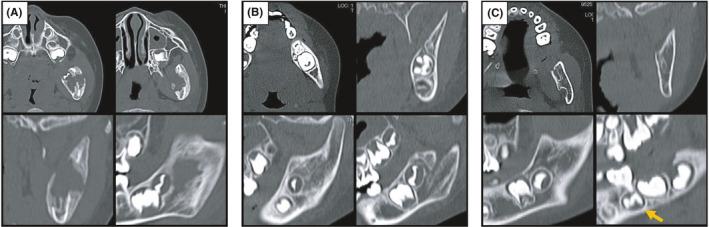

A case of langerhans cell histiocytosis of the mandible that spontaneously regressed after biopsy in a child.

In younger patients of LCH, we should consider that the effectiveness of follow-up without aggressive treatment for SS-type LCH in the oral and maxillofacial bone. However, there are very rare case in which an SS-type LCH recurred after showing a healing tendency. Regular follow-up must be performed even after healing.